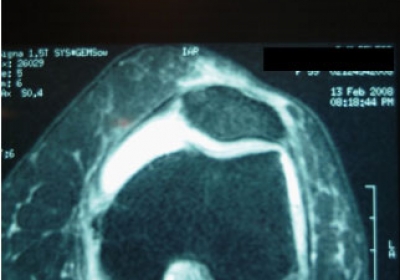

Vision en RMN: Rotura antigua del Tendon de Aquiles; antes y después de tratamiento con PRP